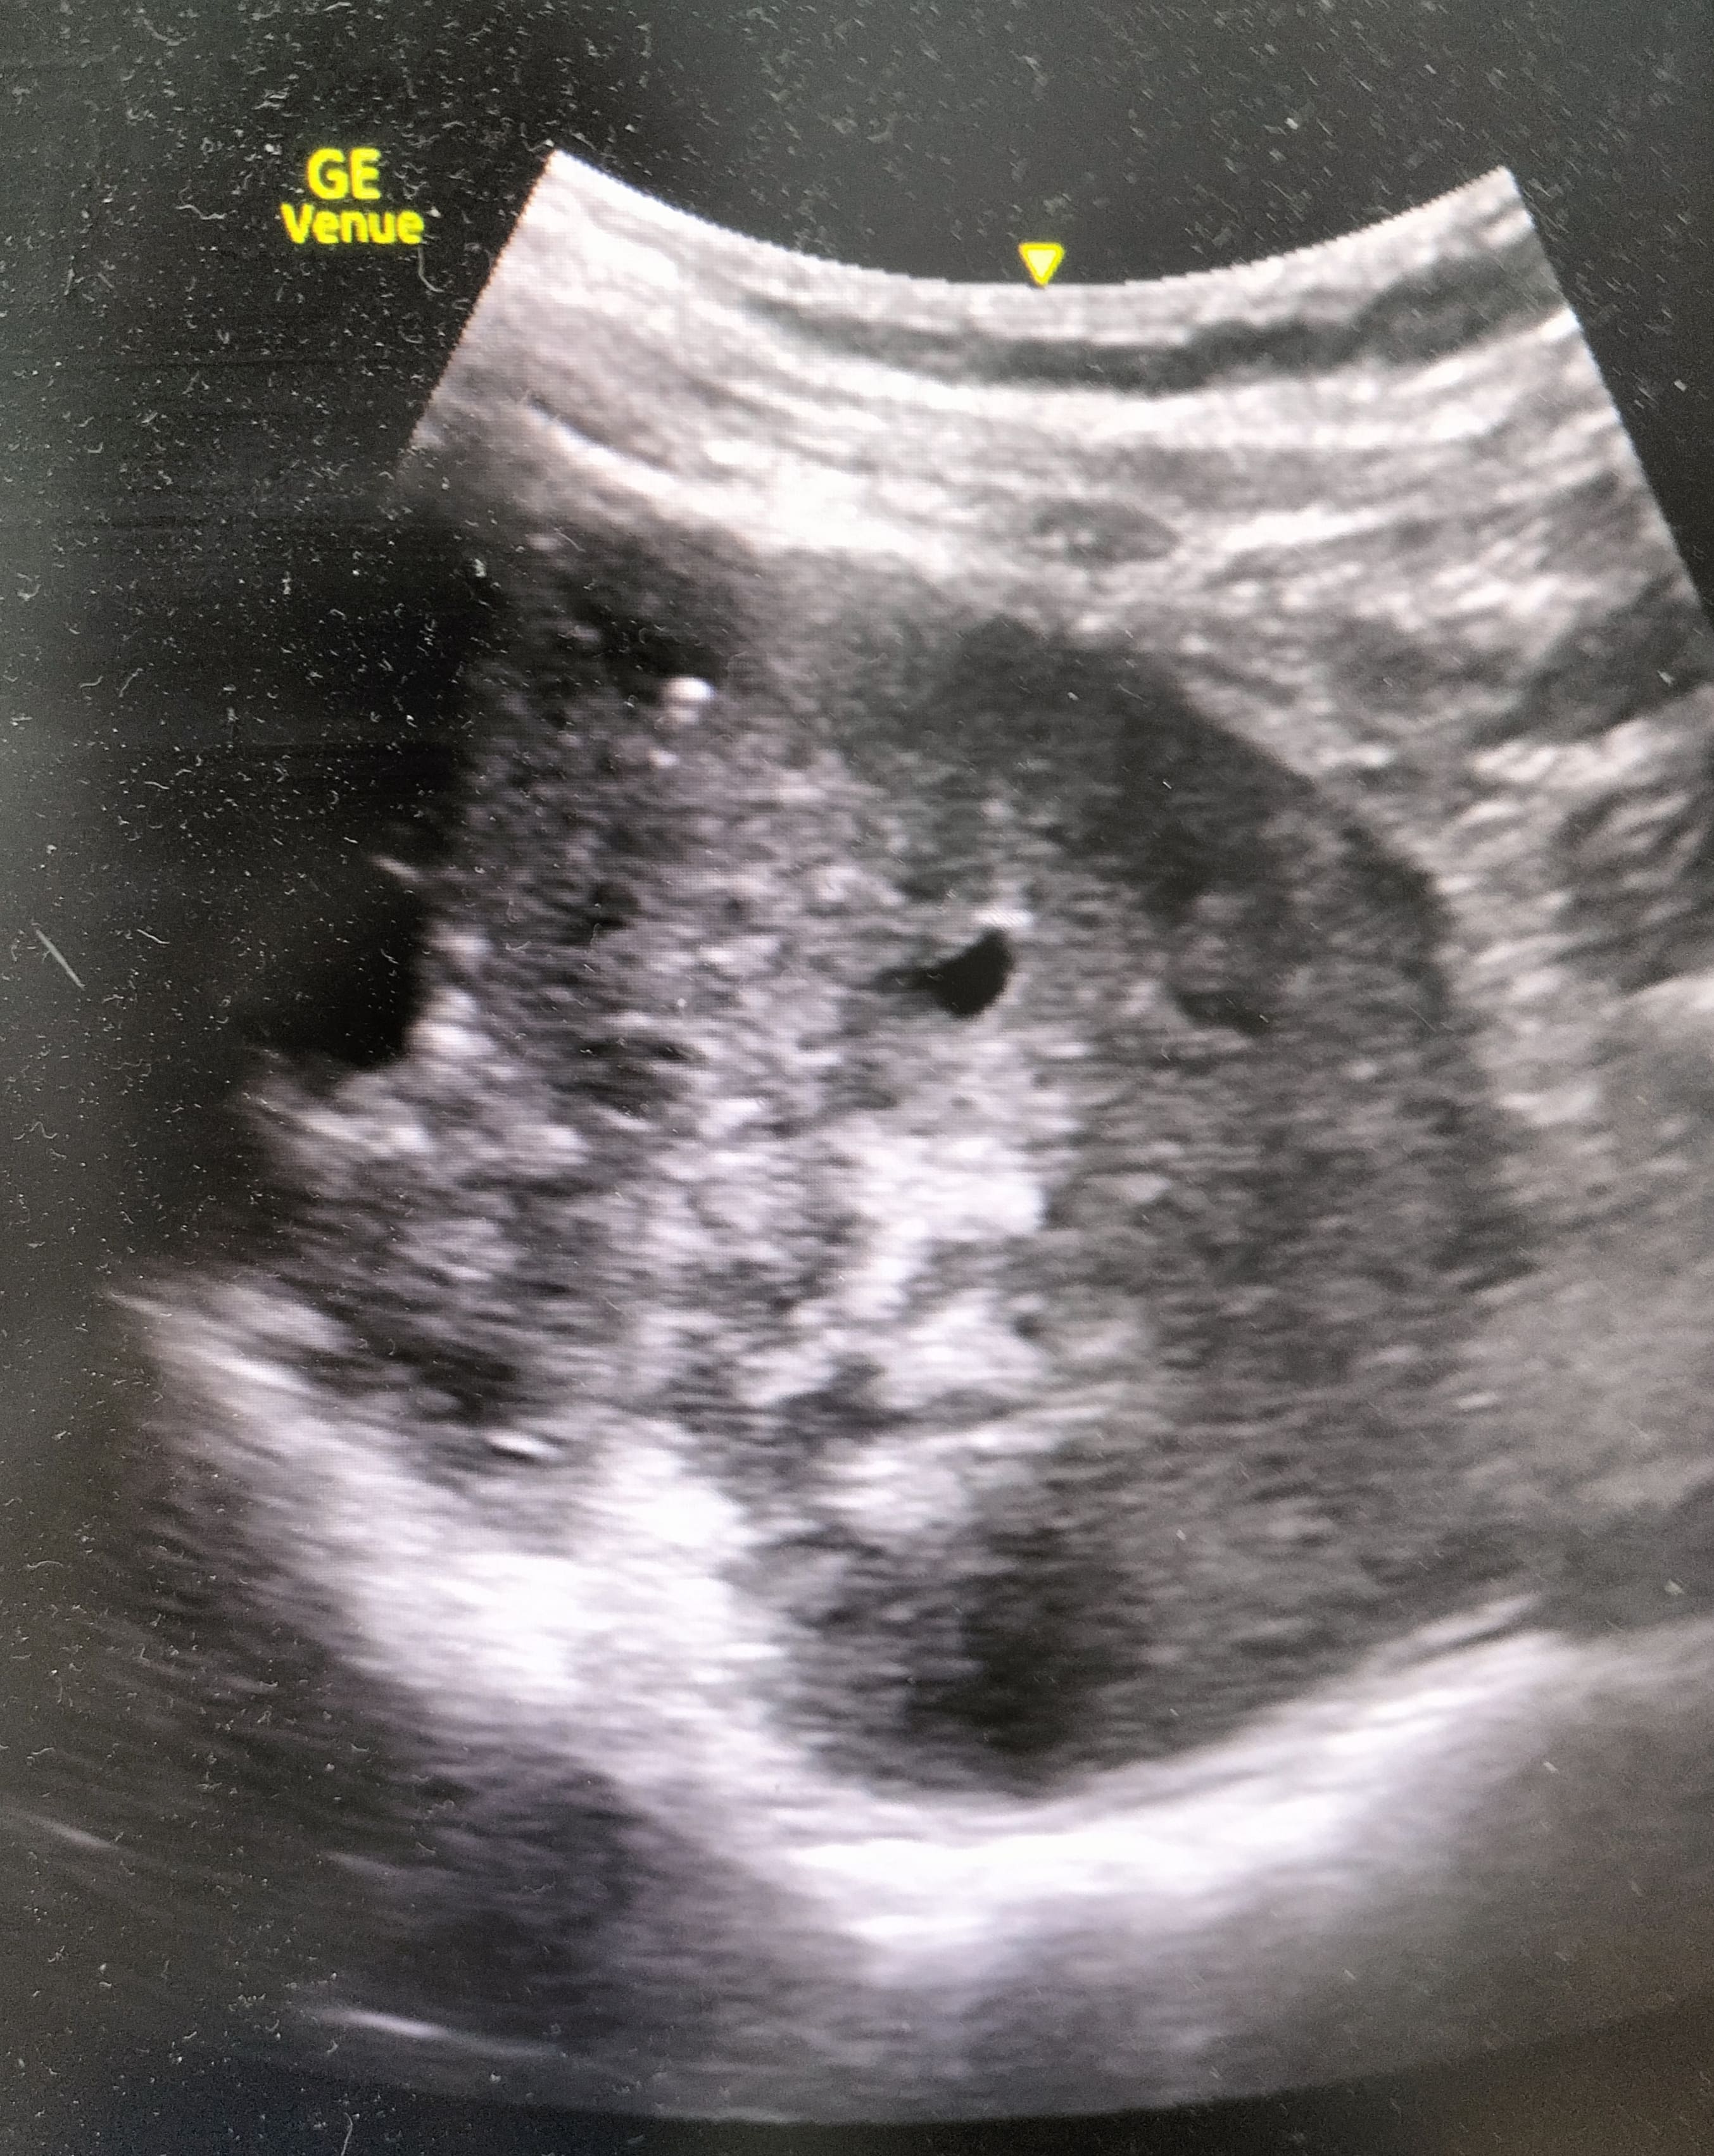

Hallazgos ecográficos

La realización de la técnica muestra riñón derecho aumentado de tamaño y una imagen compatible con una masa renal derecha con pérdida de la diferenciación cortico-medular. En contraposición se observa una silueta renal contralateral sin alteraciones.